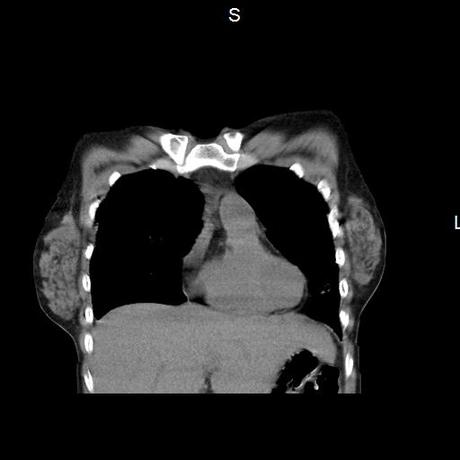

Se realiza volumen de tórax en fase simple, desde los opérculos torácicos hasta los hemidiafragmas, observándose:

La tráquea es central, con adecuada columna de aire, sin evidencia de compresiones o desplazamientos.

El mediastino es central, sin evidencia de crecimientos ganglionares.

El corazón y los grandes vasos de morfología y situación normal.

El parénquima pulmonar con areas parcheadas difusas en vidrio despulido combinadas con otras areas hipodensas de baja atenuación debidas a atrapamiento aéreo y engrosamiento intersticial y zonas de fibrosis de predominio en lóbulos medios e inferiores de ambos pulmones.

- LOS HALLAZGOS PUEDEN ESTAR EN RELACIÓN A NEUMOPATIA INTERSTICIAL PROBABLE ETIOLOGIA HIPERSENSITIVA VS AUTOINMUNE/BACTERIANA/FUNGICA.